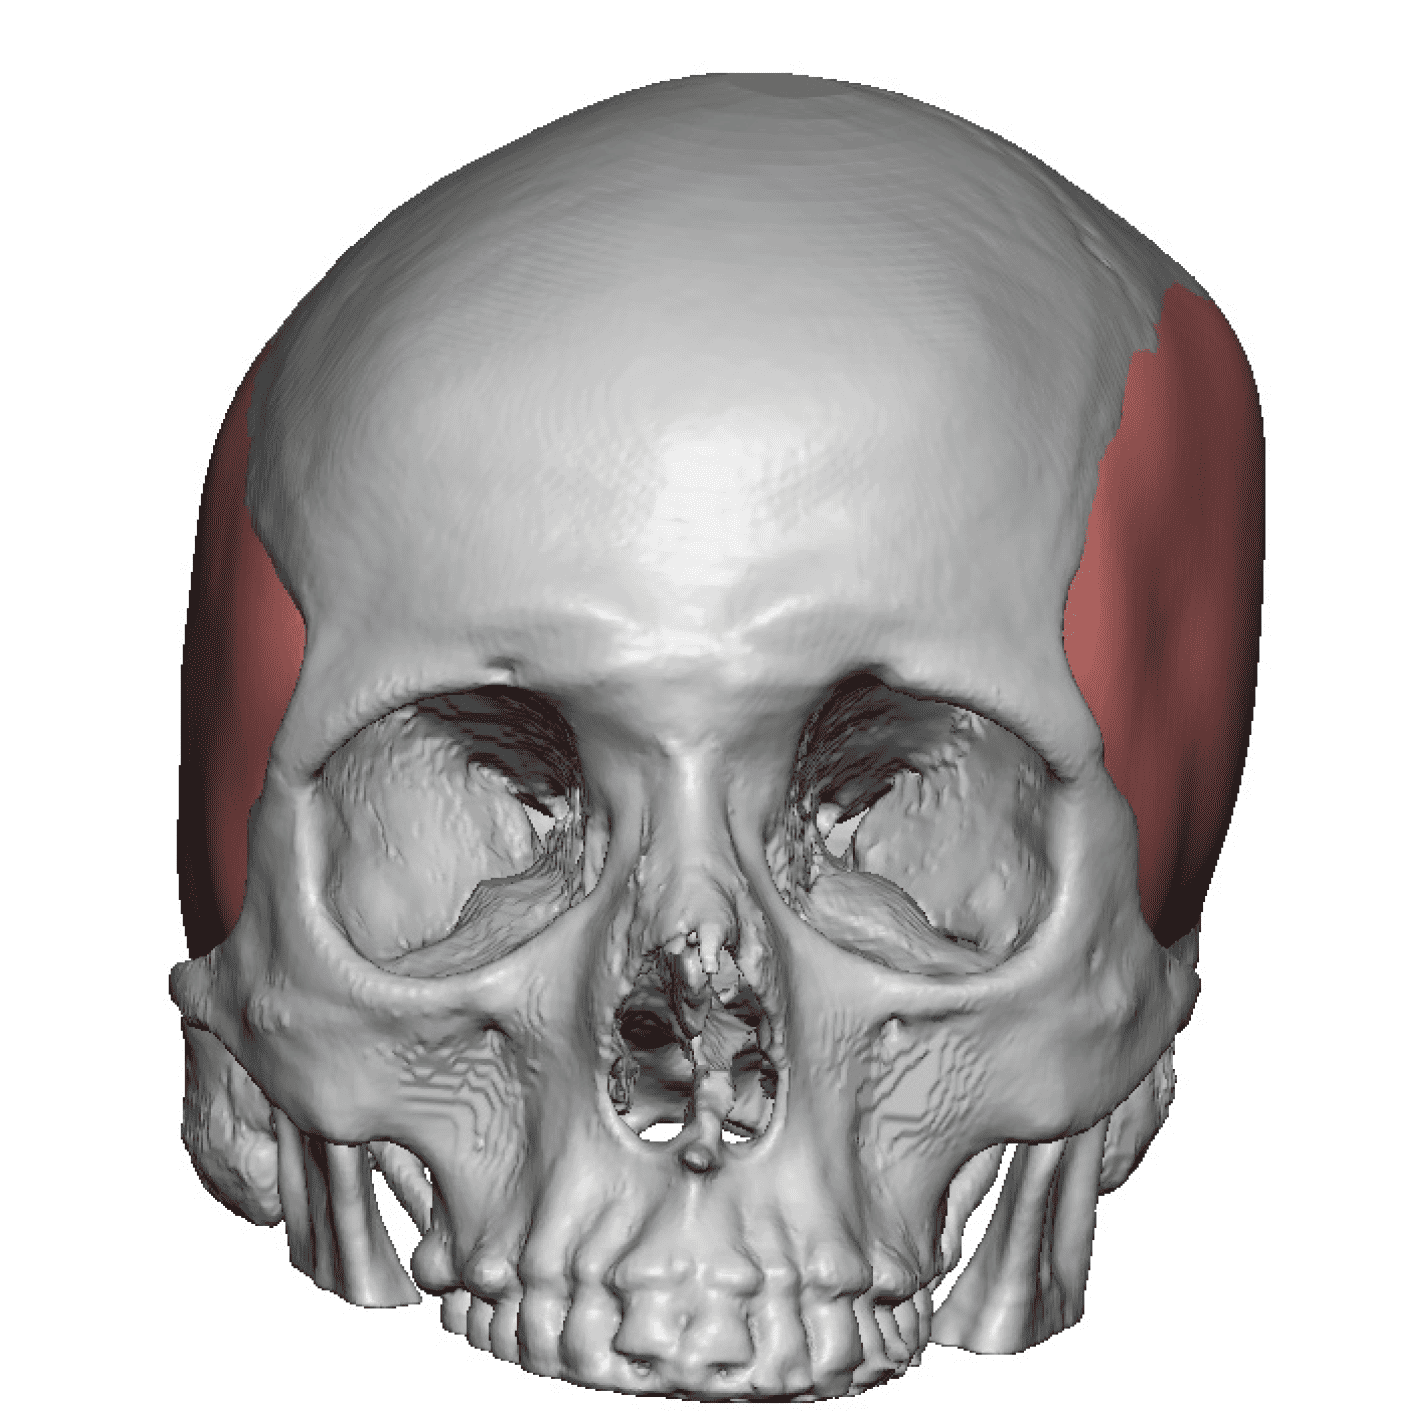

Patient 28

Desire for rounder shape to the top of the head from a congenital parasagittal deficiency skull shape.

Custom skull implant designed to fill in the parasagittal deficiencies.

Desire for rounder shape to the top of the head from a congenital parasagittal deficiency skull shape.

Custom skull implant designed to fill in the parasagittal deficiencies.